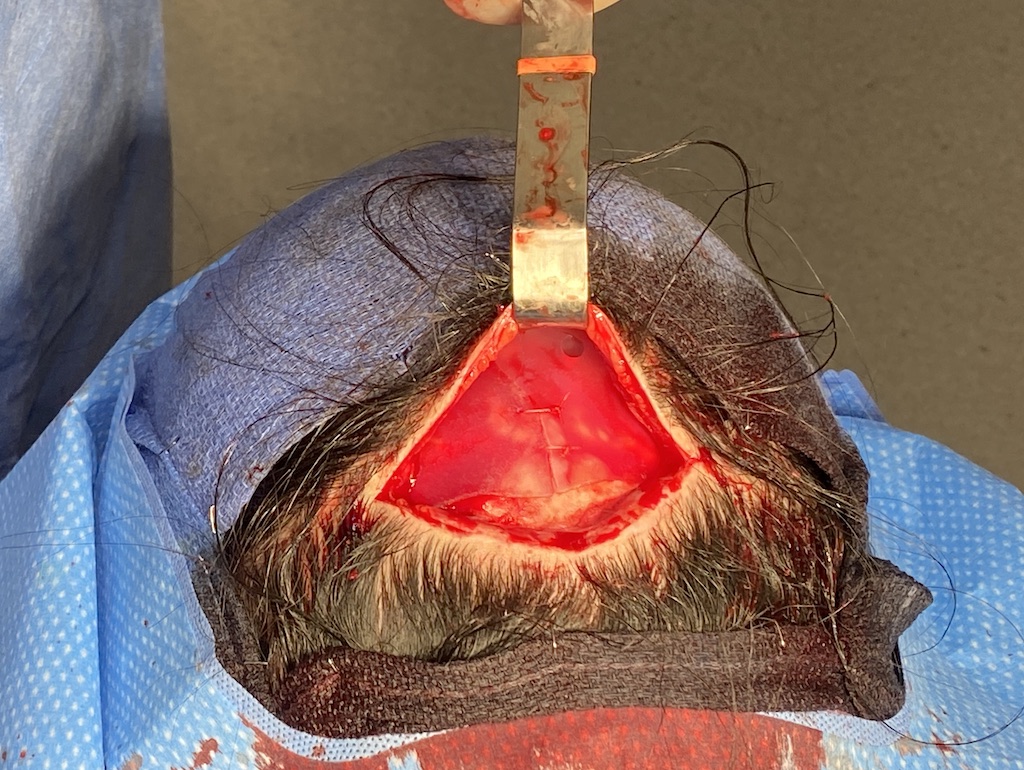

Severe narrowing skull deformity from prior sagittal craniosynostosis repair as an adult.

Complete replacement of entire skull by a custom implant with temporal fat injections.

Severe narrowing skull deformity from prior sagittal craniosynostosis repair as an adult.

Complete replacement of entire skull by a custom implant with temporal fat injections.